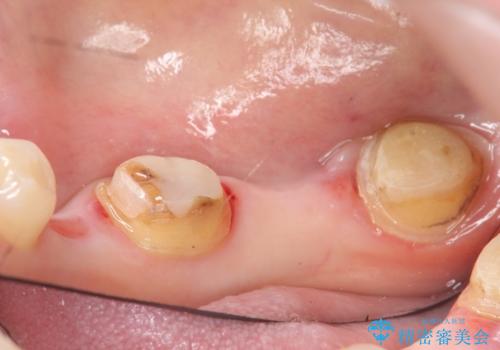

カスタムアバットメントは患者様それぞれの歯茎に合わせて製作されたオーダーメイドのアバットメントです。

既製のアバットメントに比べ適合がよく、高い清掃性を誇ります。

今回用いたオールセラミッククラウンはジルコニアフレームという白い素材の上にセラミックを盛っているため、審美性が非常に高いのが特徴です。

また、ジルコニアは人工ダイヤモンドの材料にも使われているほど高い強度を持っており、そのためオールセラミッククラウンは審美性だけでなく、奥歯やブリッジの補綴も可能とするクラウンです。